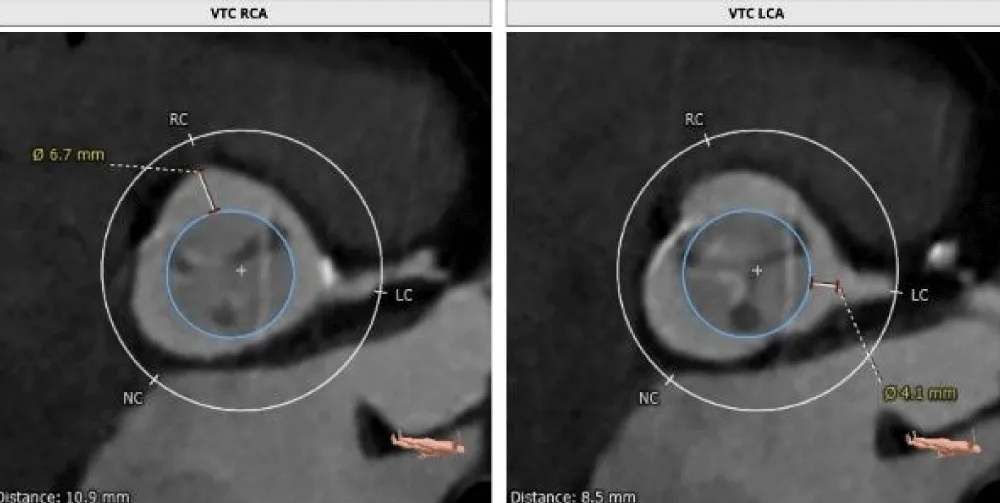

The patient’s past surgical notes were traced, which revealed that the initial AV replacement was performed using a 21 mm CROWN PRT™ stented bioprosthetic valve (LivaNova PLC, London, United Kingdom). Since the patient had high EuroSCORE II and STS scores, the Heart Team selected TAVI. Following the pre-TAVI screening, her coronary angiogram revealed non-obstructive lesions in the left anterior descending (LAD) artery. The 2-D contrast-enhanced CT and aortography revealed an average aortic annulus diameter of 21.9 mm, annular area of 381.9 mm2, and annulus perimeter of 69.4 mm, as seen in Figure 2a. The sinus of Valsalva (SOV) diameters of the left, right, and non-coronary cusps were 27.4 mm, 28 mm, and 31.6 mm, respectively (Figure 2b). However, the right and left coronary ostial (LCO) heights were 10 mm and 6.8 mm, respectively, both being abnormally low including the critically short LCO that was well visualized on CT (Figure 2c,2d). The SOV height was 9.3 mm and the height of the sino-tubular junction (STJ) was 13.1 mm (Figure 2e), while the average diameter of the STJ was 28.2 mm. In terms of access, both the femoral and iliac arteries had acceptable diameters on both sides without severe calcification showing suitability for a transfemoral approach (Figure 2f). On 2D-CT, the predicted VTC distance was 6.7 mm for the right coronary ostia (RCO) and 4.1 mm for the LCO, if a 21.5 mm Myval THV was used (Figure 3). The 21.5 mm BE Myval (Meril Life Sciences Pvt. Ltd., Vapi, India) was selected to be deployed under rapid pacing.

Figure 3: Showing the VTC reconstructed on 2D-CT (left: 6.7 mm; right: 4.1 mm) with the implantation of the selected 21.5 mm Myval THV.